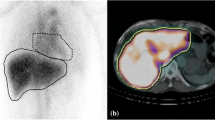

To assess the utility of a machine-learning approach for predicting liver function based on technetium-99 m-galactosyl serum albumin (99mTc-GSA) single photon emission computed tomography (SPECT)/CT.

One hundred twenty-eight patients underwent a 99mTc-GSA SPECT/CT-based liver function evaluation. All were classified into the low liver-damage or high liver-damage group. Four clinical (age, sex, background liver disease and histological type) and 8 quantitative 99mTc-GSA SPECT/CT features (receptor index [LHL15], clearance index [HH15], liver-SUVmax, liver-SUVmean, heart-SUVmax, metabolic volume of liver [MVL], total lesion GSA [TL-GSA, liver-SUVmean × MVL] and SUVmax ratio [liver-SUVmax/heart-SUVmax]) were obtained. To predict high liver damage, a machine learning classification with features selection based on Gini impurity and principal component analysis (PCA) were performed using a support vector machine and a random forest (RF) with a five-fold cross-validation scheme. To overcome imbalanced data, stratified sampling was used. The ability to predict high liver damage was evaluated using a receiver operating characteristic (ROC) curve analysis.

Okabayashi T, Shima Y, Morita S, et al (2017) Liver function assessment using technetium 99m-Galactosyl single-photon emission computed tomography/CT fusion imaging: a prospective trial. J Am Coll Surg 225:789-797

Yoshida M, Beppu T, Shiraishi S, et al (2015) (99m)Tc-GSA SPECT/CT fused images for assessment of hepatic function and hepatectomy planning. Ann Transl Med 3:17